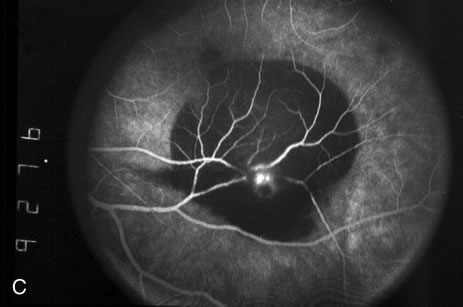

Retinal arterial macroaneurysms usually arise within the first three orders of bifurcation from the optic disc (Fig. 2), often at a point of arteriovenus crossing. Sometimes they occur directly on the optic nerve head3 or on a cilioretinal artery.4 About 20% of affected eyes have multiple aneurysms, and about 10% demonstrate macroaneurysms in both eyes.

Fig. 2. A. Color fundus photograph of a 200-micron macroaneurysm that arises from a retinal artery near the optic disc with thin subretinal hemorrhage that does not threaten the fovea. B. The midphase fluorescein angiogram reveals blockage of choroidal but not retinal vascular hyperfluorescence. C. The late-phase angiogram demonstrates staining of the macroaneurysm.[pa[et[ol0]